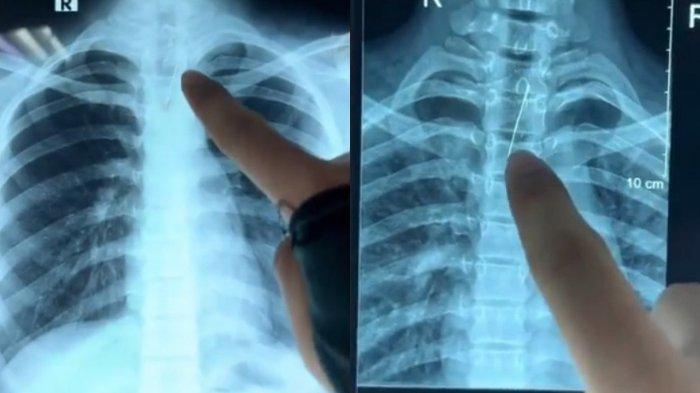

Video berdurasi 25 detik itu menayangkan hasil rontgen pasien. Ternyata pasien tersebut menelah sebuah jarum yang akan digunakannya di jilbabnya.

Video berdurasi 25 detik itu menayangkan hasil rontgen pasien.

Ternyata pasien tersebut menelah sebuah jarum yang akan digunakannya di jilbabnya.

Jarum itu ia gigit dan tak sengaja masuk dalam mulut hingga tertelan.

Dalam keterangannya jarum yang tertelan itu menyangkut di tenggorokan pasien.

Tepatnya berada di saluran pernafasan atau trakea sang wanita.

Terlihat jarum yang tertelan itu tak panjang, namun bisa berdampak fatal.

Sehingga pihak RSUD Kabupaten Jombang akan melakukan operasi untuk mengeluarkannya.

Pasien menggigit jarum saat memasang jilbab dan jarumnya masuk ke mulut lalu tersedak.

Setelah dilakukan pemeriksaan ternyata jarumnya berada di saluran napas (trakea) dan harus diambil dengan operasi.